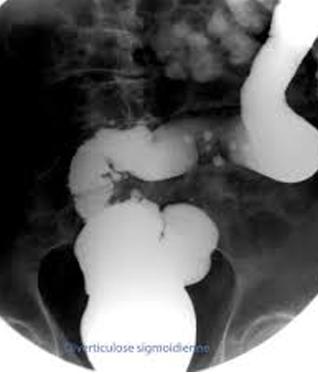

Aspect radiologique de lavement baryte est :

- Sur le lavement baryte mono de contrast

:C'est image sacculaire en plein de

baryum de la diverticule au paroi du colon "

outpouching sign" . |

Image radiologique de

diverticule du colon sigmoide . Image en sacculaire

des diverticules en pleine de baryte a difference

taille au long du colon sigmoide . Image de "outpouching

sign " |

Diverticulose colique : Les

diverticules a difference taille s'etendue le long

du colon sigmoide , colon descendant et colon

transverse ( fleche rouge ) Image en spastique du

colon sigmoide ( fleche jaune ) peu se voyait

nettete . Image lavemevt baryte mono de contrast . |